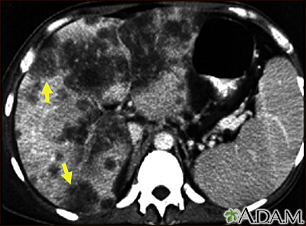

Hepatocellular cancer - CT scanBackHepatocellular cancer - CT scanA CT scan of the upper abdomen showing a widespread (disseminated) carcinoma of the liver (hepato cellular carcinoma). The liver is the large organ on the left side of the picture. Note the moth-eaten appearance. E-mail FormEmail ResultsName:Email address:Recipients Name:Recipients address:Message: